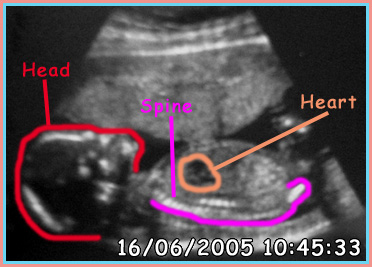

29/04/2005

Wk 14 - The Scans

As of 29/04/2005 we have three scans done at Burnely General Hospital. I have tried to keep them as clear as possible. Since any bright light or scanning would turn the photos black.

I have also marked out each section on a second picture showing you what is what, as they can be confusing to look at.

The scans have been placed in order they have been taken.

Labels of the Scan